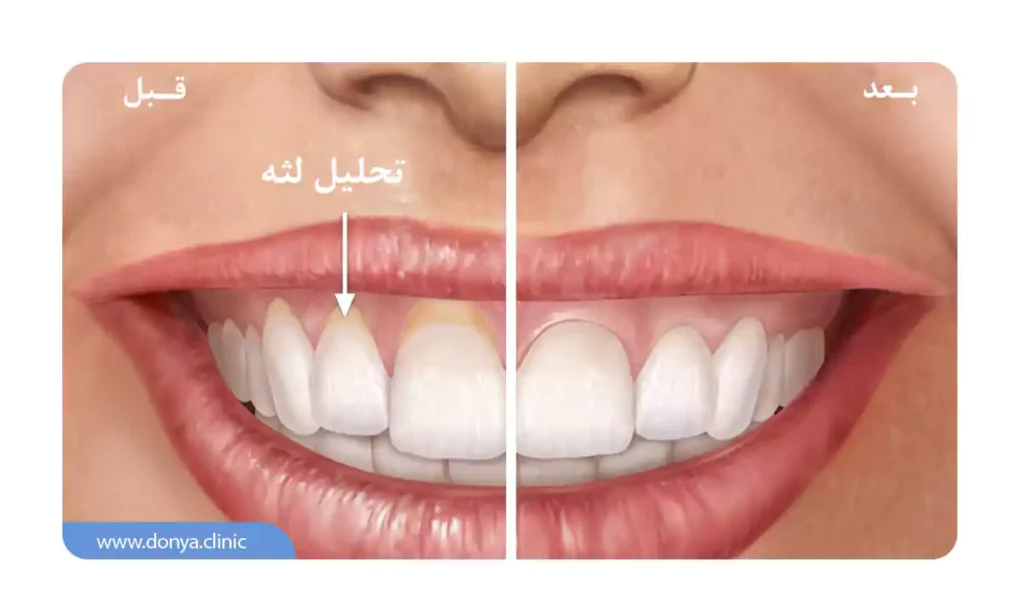

تحلیل لثه یا (Gum recession) نوع رایجی از مشکلات دندانپزشکی است که در آن، حاشیه بافت لثه (که دندان ها را احاطه کرده) از بین رفته یا نازک می شود. اصطلاحاً به این مشکل عقب نشینی لثه نیز گفته می شود. زمانی که لثه تحلیل می رود، ریشه دندان ها نمایان می شود و مشکلات زیادی برای افراد ایجاد می شود.

اولین علامت عقب نشینی لثه معمولاً حساسیت دندان است. به جز این ممکن است متوجه شوید ریشه دندان در معرض دید قرار گرفته یا طول دندان کمی بیشتر از چیزی شده که قبلا بود.

- منقبض شدن مشهود لثه ها که در آن لثه ها به نظر کوچک تر و دندان ها بلندتر به نظر می رسند.

- مشخص شدن ریشه های دندان که توسط لثه پوشیده می شوند.